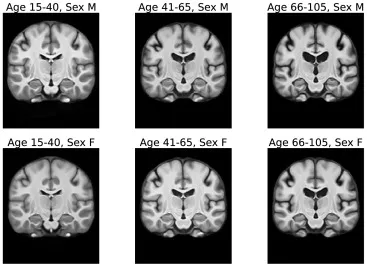

图18我们的配准基线中使用的ANTs-Frag-no-Seg迭代模板。这些模板是通过对按年龄和性别划分的六个不同人群亚组应用ANTs SyGN算法构建的。每个组有100名受试者。

研究结果显示,AtlasMorph生成的模板明显比简单平均法获得的模板更清晰。条件模板成功捕捉了与年龄相关的萎缩现象,如脑室增大和海马体缩小,这与已知的群体趋势一致。在配准性能方面,AtlasMorph模型在Dice评分和表面距离上持续优于所有基线方法,包括ANTs和Aladdin变体。联合学习标签图与强度模板显著提高了性能,且条件变体略优于无条件变体。尽管年轻受试者的分割结果相对较差,可能与数据不平衡有关,但AtlasMorph在所有年龄段均表现最佳。变形场规则性良好,雅可比行列式的负值数量微不足道,表明其具有解剖学上的合理性。新的中心性损失公式使AtlasMorph比LT2019模型更能准确捕捉群体趋势,这在脑室和海马体体积分析中得到证实。此外,使用100个受试者平均值进行初始化比单个随机受试者初始化能获得更稳定、更优异的结果。AtlasMorph还成功学习了结合认知障碍(AD、MCI、CN)等额外属性的模板。